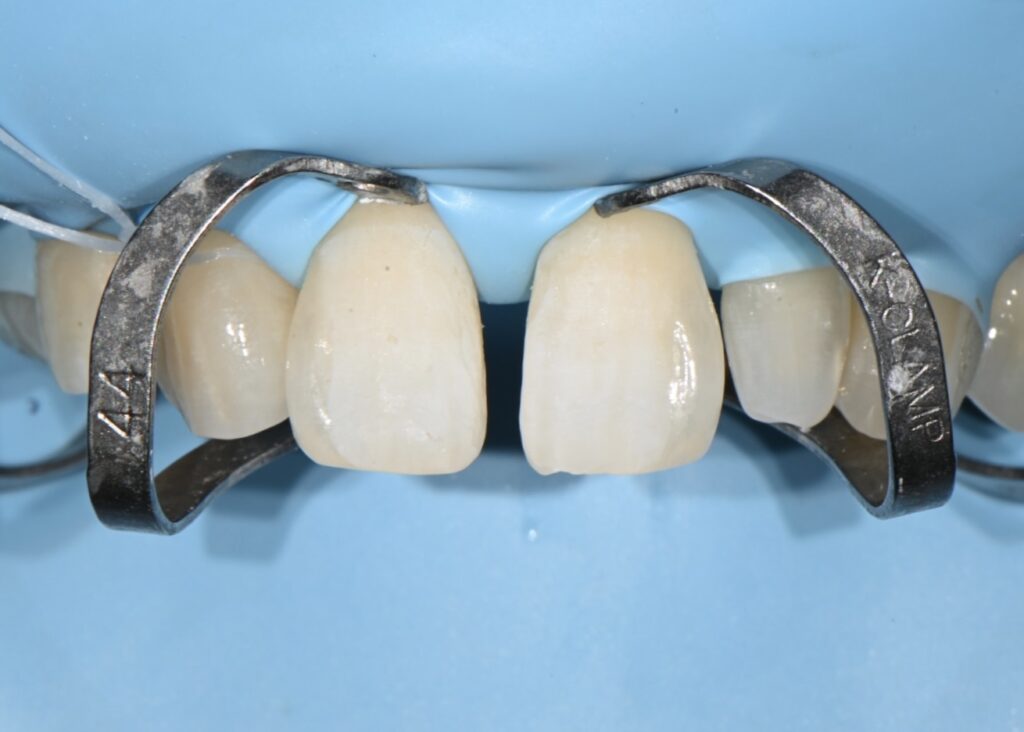

레진 치료의 첫번째 철저한 방습

레진 치료의 가장 중요한 부분은 방습인데요

침이나 수분에 굉장히 취약한 부분이기에

레진이나 라미네이트 모두 철저한 방습이 필수입니다

깨끗하게 처리한 후 러버댐으로 방습을 시행하였습니다

저렇게 클램프라는 고리로 치아에 거는 이유는

치아의 끝부분까지 자연스럽게 레진으로 충전하기 위해서입니다